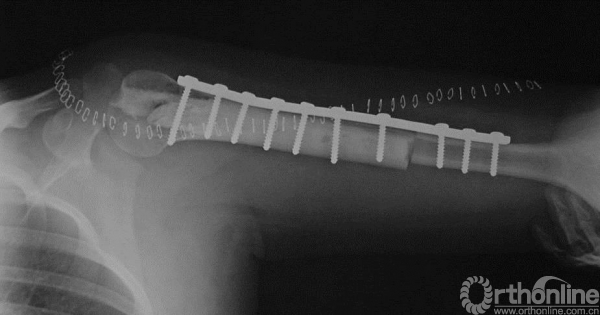

图13-5 病例一术后X线平片正侧位

术后病理报告示“倾向于侵袭性骨母细胞瘤”。

患者术后4个月发现原手术切口出现包块。